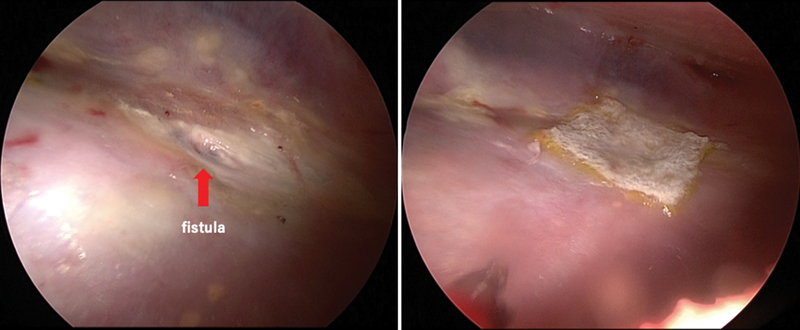

Background  No consensus exists regarding surgical intervention for rheumatoid nodule-related pneumothorax. Clinical policy decisions rely on individual clinicians' experience and are usually intractable. Case Description  A 50-year-old man with a difficult-to-treat rheumatoid arthritis-related pneumothorax was successfully treated with pedicle omentoplasty without recurrence at approximately 2 years posttreatment. To the best of our knowledge, this is the first report of a patient where pneumothorax did not recur due to firm adhesions despite fluctuating postoperative rheumatoid nodules, as captured by regular computed tomography imaging follow-ups. Conclusion  Pedicled omentoplasty is effective for rheumatoid nodule-related pneumothorax as it reduces pneumothorax recurrence.